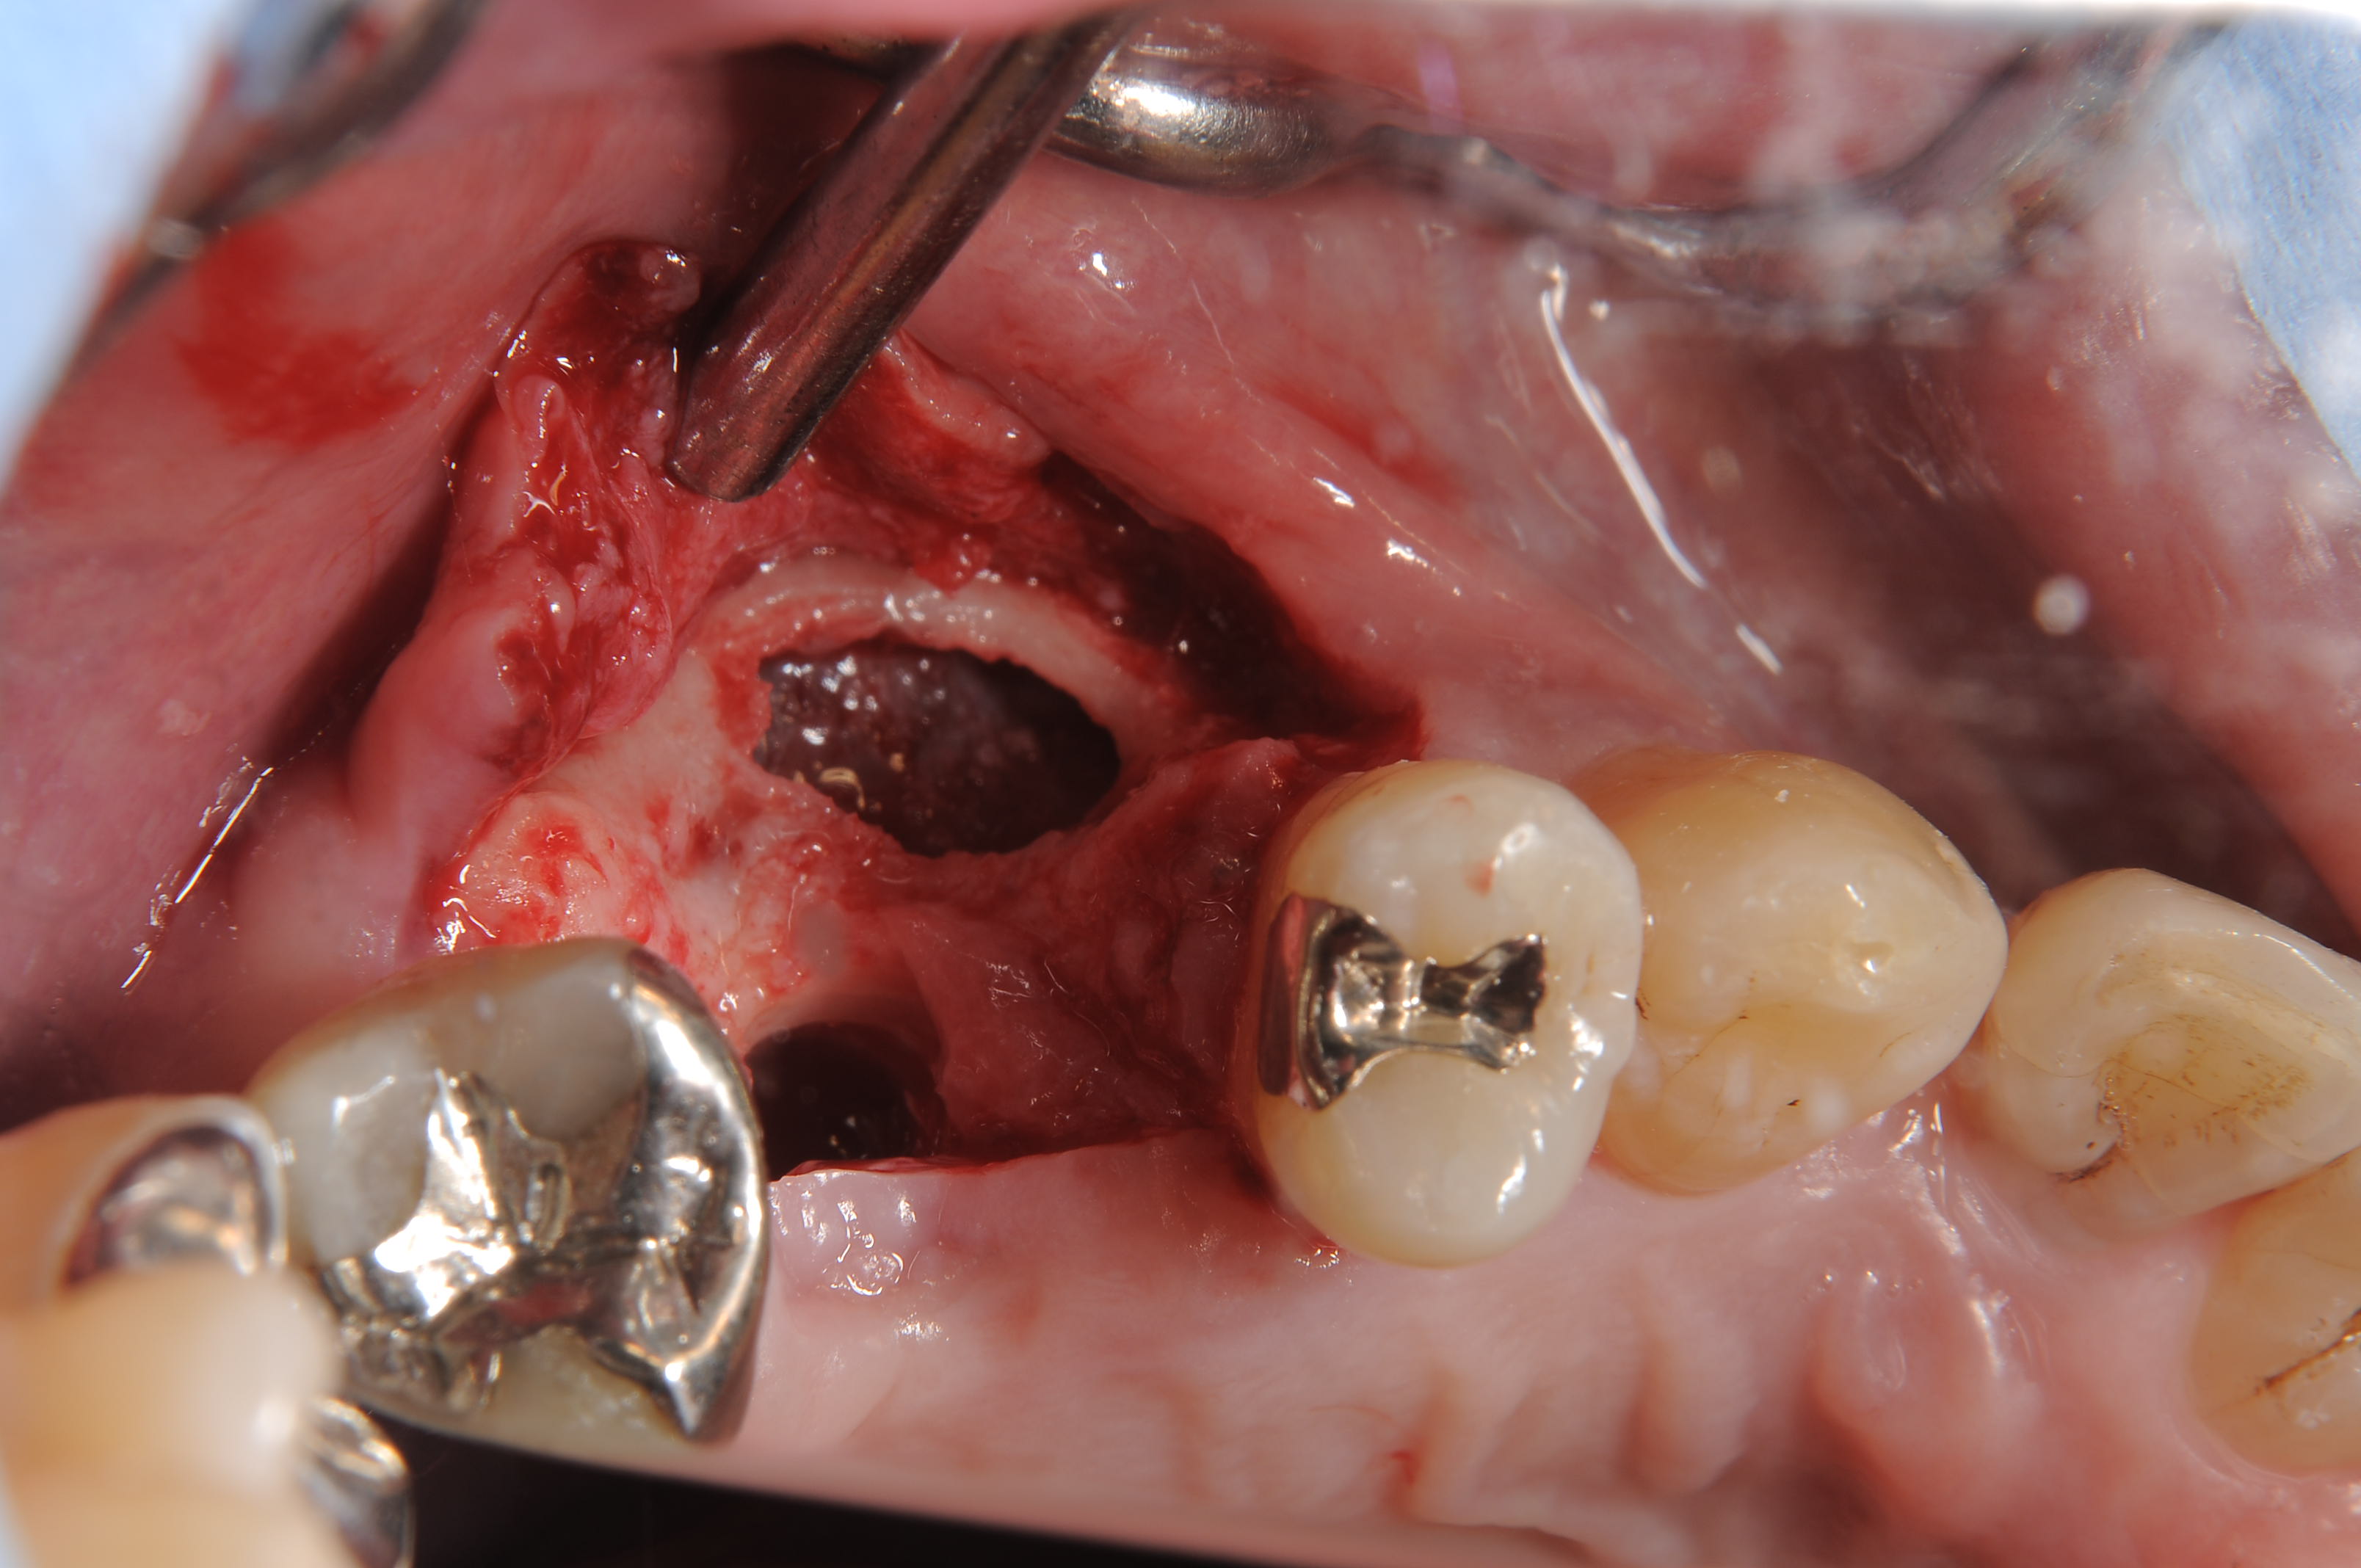

ウィンドウを開けて、歯槽頂にインプラント埋入窩を形成しました。